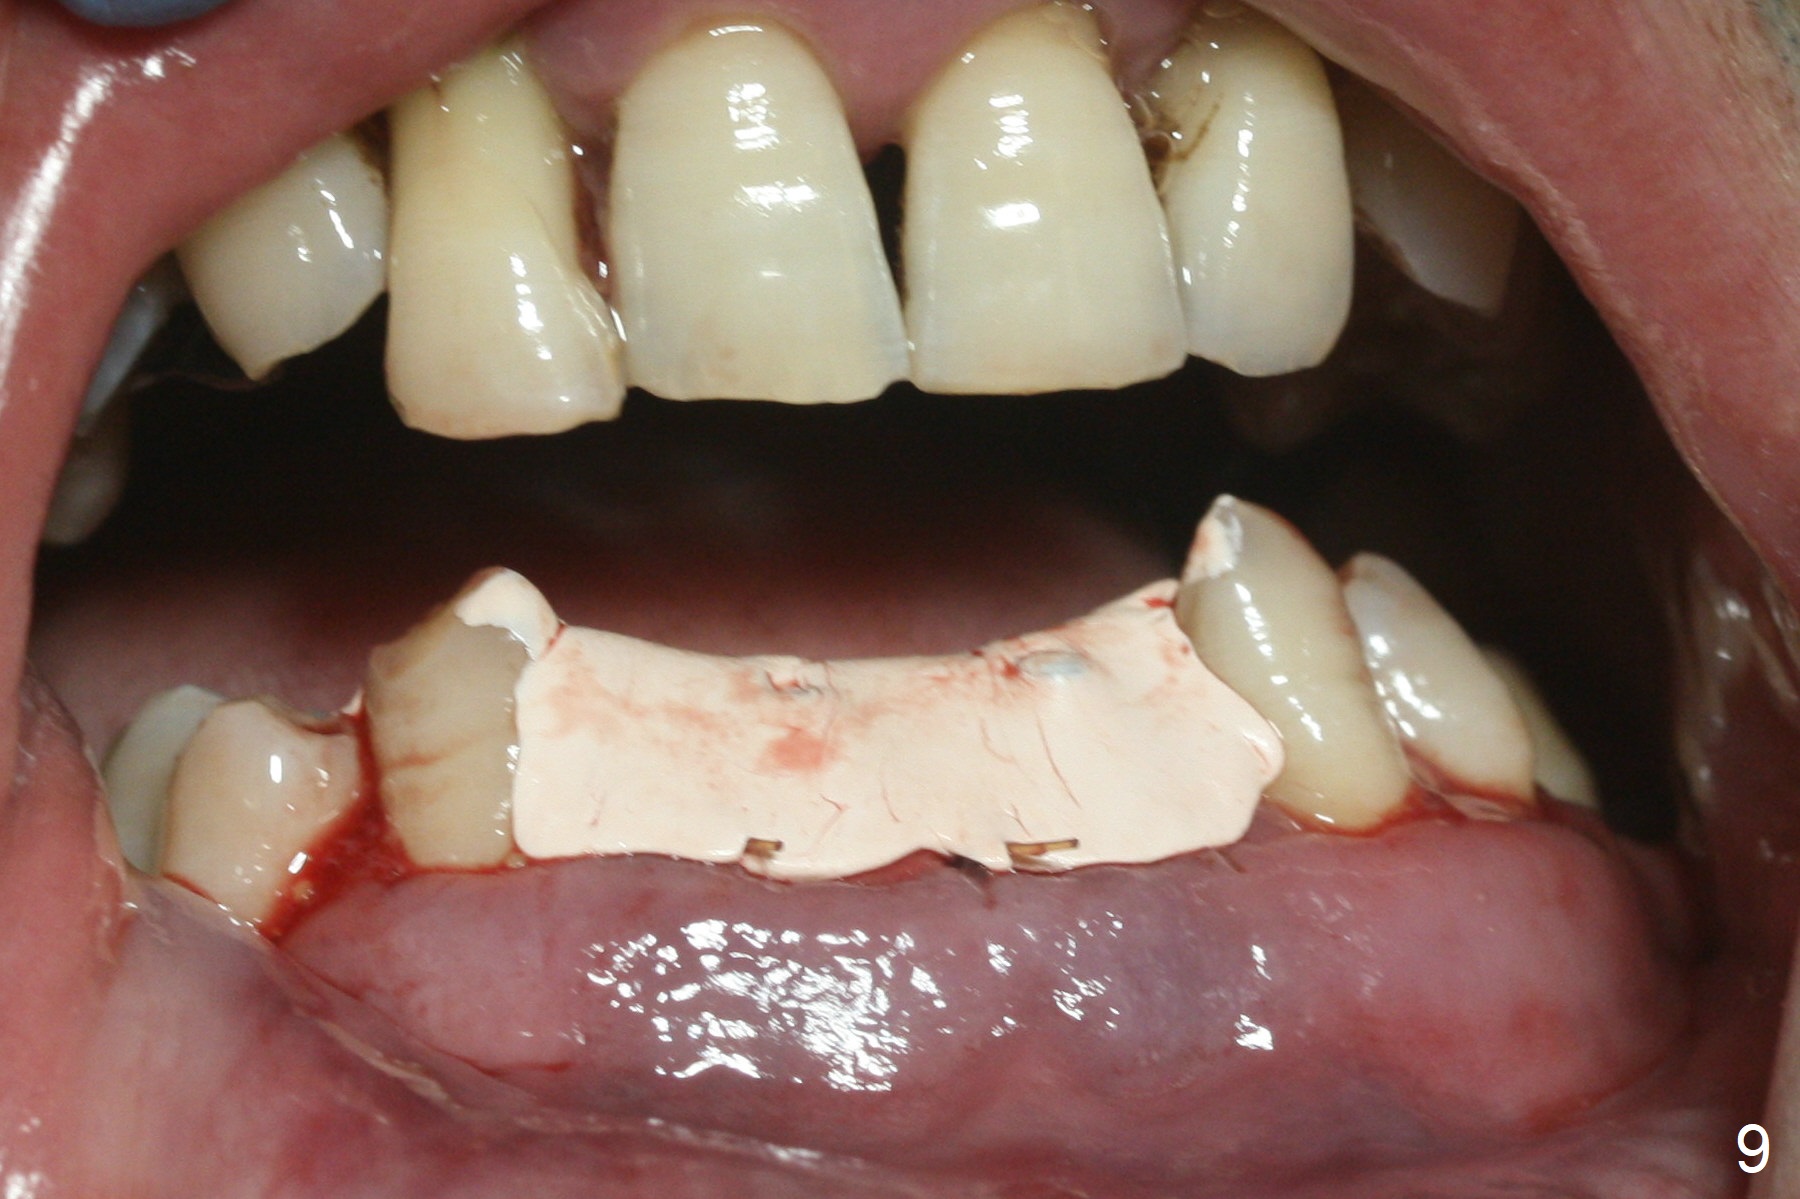

After extraction of 4 of the lower incisors, there are basically 2 sockets (#23/24 and 25/26), separated by the apparently midline bone (Fig.1 red line). In spite of using Lindamann bur to move the 25/26 osteotomy mesially, a 3x14(2) mm dummy implant remains close to the tooth #27 (Fig.2). The terminal branch of the Incisive Canal (<) is located between the lateral and central incisors. A de novo osteotomy (Fig.3 (1.5 mm drill)) is made mesial to the original one (O). While the 3x14(2) mm dummy implant is incompletely placed at #25/26, a 3x14(4) mm 1-piece one is placed at #23/24 (Fig.4). Finally the same implant is placed at #25/26 with placement of mineralized cortical/cancellous bone (Fig.5 *). When the large sockets are sutured, the supraerupted teeth #7-9 touch the lower gingiva (Fig.6). The incisal edge is reduced for clearance (Fig.7). Periodontal dressing is less likely to be dislodged with the incisal edge reduction (Fig.8,9). A provisional FPD is fabricated 1 week postop. Hard (Fig.10) and soft (Fig.11,12) tissues heal 5.5 months postop. The patient returns for crown cementation 3 months post impression (9 months postop, Fig.13,14).